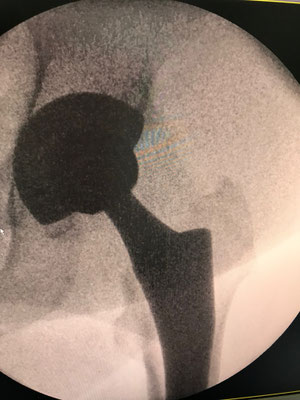

An der Hüfte setzen wir auf langjährig bewährte Implantate, die nachweislich über Jahrzehnte gute Ergebnisse liefern. Wir versuchen, wenn möglich, größere Standardkugeln einzusetzen um eine möglichst gute Beweglichkeit zu erreichen. Leider hatten bisherige "moderne" neue Hüftgelenke immer wieder Probleme, sodaß diese relativ schnell vom Markt wieder verschwanden ( z. B. Roboterhüfte, Computer designed Prothese, Oberflächenersatz).

Jede Hüftprothese wird zuvor, wie in einem Ingenieurbüro am Computer geplant (siehe Bild im Link Praxis) und ausgemessen, um diese Werte möglichst in der Operation umzusetzten. Ziel ist es, ihr eigenes Gelenk so zu ersetzen, daß ihr Muskelzug und Kraftübertragung erhalten bleibt und die Prothese optimal eingepaßt wird.

Die SUPERPATH Hüfte : In günstigen Fällen wird das künstliche Gelenk in einem minimalen Verfahren von oben hinten eingebaut. Die Vorteile: keine Muskelabtrennung, Erhaltung der Hüftkapsel, die Hüfte muss nicht während der Operation ausgekugelt werden. Dadurch kann frühzeitig auf Krücken verzichtet werden, der Blutverlust ist sehr gering, Thrombose und Gefahr der Ausrenkung sehr gering im Vergleich zu anderen Methoden.